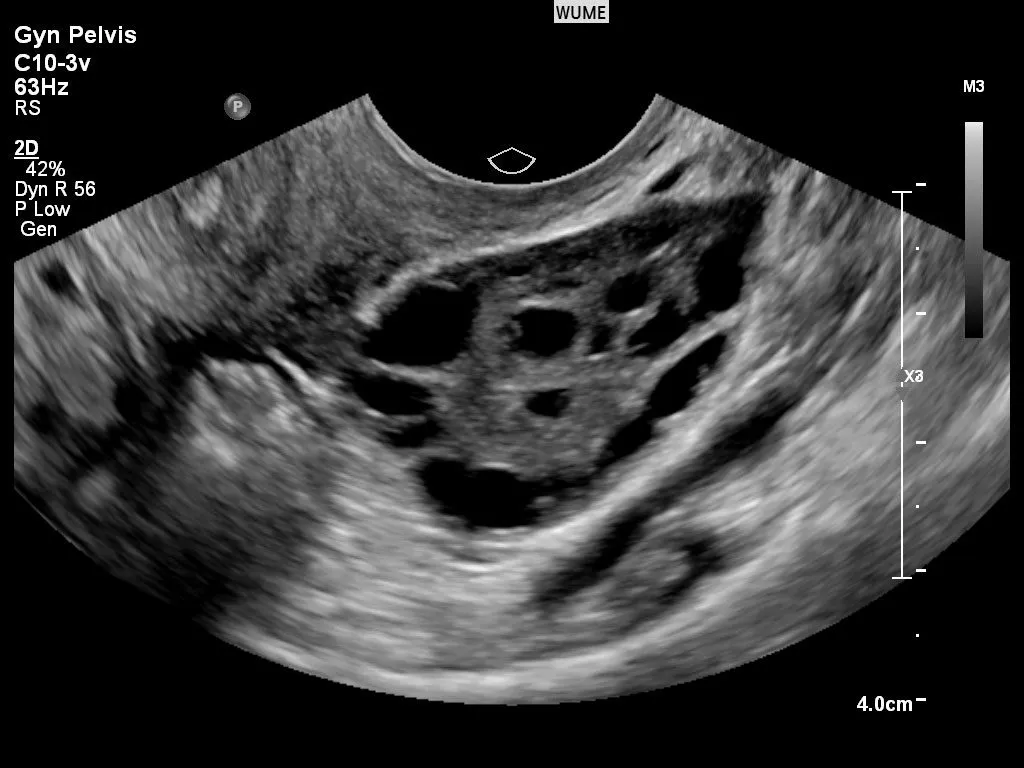

• أكياس صغيرة على المبايض تظهر عادة بالموجات فوق الصوتية

3. الموجات فوق الصوتية: فحص المبايض